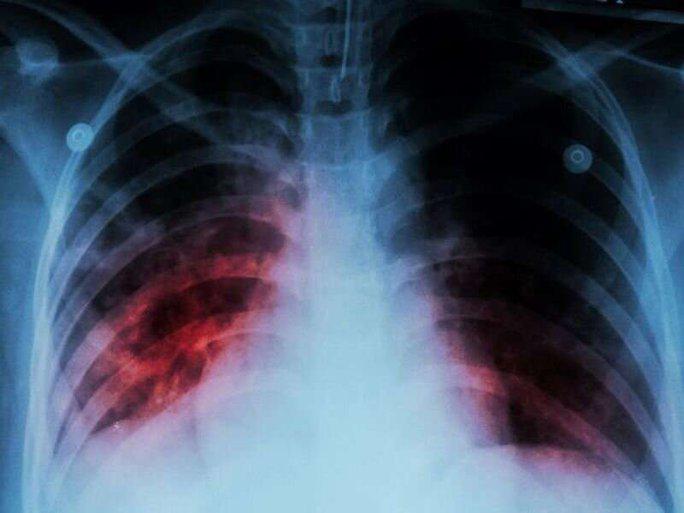

Old  Default WHO: Một bệnh cũ trỗi dậy sau 20 năm, đang gây tử vong nhiều hơn COVID-19

Theo báo cáo của Tổ chức Y tế thế giới (WHO), năm vừa qua là lần đầu tiên sau gần 2 thập kỷ số ca mắc bệnh lao, số ca lao đa kháng thuốc và tử vong do lao đều tăng.

Báo cáo được phát hành nhân Ngày Thế giới phòng chống lao (24-3) của WHO cho biết hàng năm vẫn có trung bình 1,6 triệu người chết do bệnh lao.

Con số này còn cao hơn số tử vong do một bệnh hô hấp đáng sợ khác hiện nay - COVID-19 - với báo cáo tử vong hiện đã về dưới 10.000 ca/tuần.

Đáng lo hơn, theo Tổng Giám đốc WHO Tedros Adhanom Ghebreyesus, đại dịch COVID-19 cùng với các cuộc khủng hoảng đang diễn ra như xung đột, mất an ninh lương thực, biến đổi khí hậu... đã đảo ngược tiến bộ đạt được trong nhiều năm trong cuộc chiến chống bệnh lao, khiến năm 2022 trở thành năm đầu tiên sau gần 2 thập kỷ căn bệnh này gia tăng cả số ca mắc, số ca lao đa kháng thuốc và số ca tử vong.